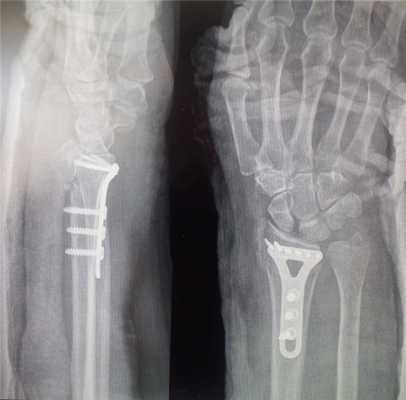

Оперативное лечение перелома лучевой кости в типичном месте (остеосинтез)

Практически все переломы лучевой кости со смещением требуют оперативного лечения - сопоставления и фиксирования отломков кости - остеосинтеза. Именно этот метод позволяет восстановить функцию кисти наиболее полноценно и добиться хороших функциональных результатов.

В зависимости от типа перелома (оскольчатый, многооскольчатый, со значительным или незначительным смещением) можно выделить несколько возможных вариантов фиксации - пластиной, фиксированной винтами; аппаратом внешней фиксации; винтами; спицами.

Остеосинтез лучевой кости пластиной

При значительном смещении отломков используется остеосинтез лучевой кости металлической пластиной, специально изготовленной для данного сегмента. После сопоставления отломков пластина фиксируется винтами к поврежденной кости. После установки пластины накладываются на кожу накладываются швы на 2 недели, а также гипсовая лонгета примерно на тот же срок. После операции назначается лекарственная терапия: обезболивающие препараты, препараты кальция для более быстрого срастания костей, при необходимости - препараты местного действия для уменьшения отека. Средний срок пребывания в стационаре - 7 дней. Швы снимаются в амбулаторном режиме спустя 2 недели. Рука носится в возвышенном положении на косыночной повязке. Необходимости в удалении пластины нет.